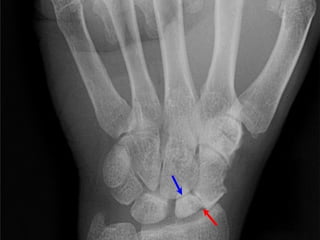

Radiography

 The 4 essential views (ie, PA, lateral, supinated and

pronated obliques) identify majority of fractures.

 The scaphoid view is a PA radiograph with the wrist

extended 30° and deviated ulnarly 20°. This view

helps to stretch out the scaphoid and is also used for

assessing the degree of scaphoid fracture angulation.

 A clenched-fist radiograph has also been useful for

visualization of the scaphoid waist.

Radiography  The 4essential views (ie, PA, lateral, supinated and pronated obliques) identify majority of fractures.  The scaphoid view is a PA radiograph with the wrist extended 30° and deviated ulnarly 20°. This view helps to stretch out the scaphoid and is also used for assessing the degree of scaphoid fracture angulation.  A clenched-fist radiograph has also been useful for visualization of the scaphoid waist.